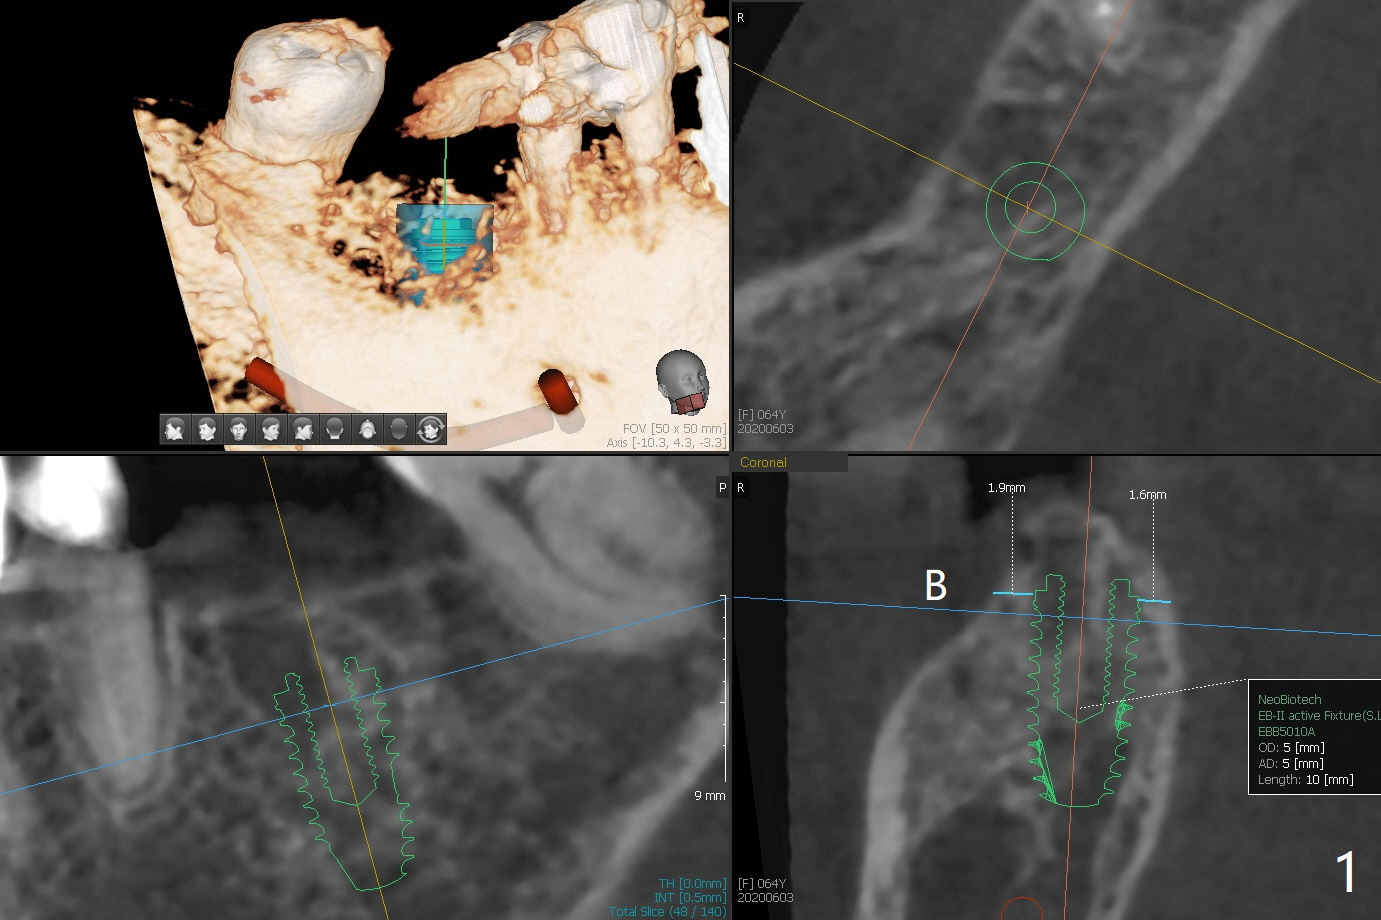

A 64-year-old woman with partial edentulism requests an implant for #30 after #29 crown temp bond cementation (Fig.1). The buccal, crestal and lingual cortex is equally thin (no deviation). The medulla is porous. The average bone density is 600 units. Ask the patient about osteoporosis treatment. A 4.5x10 mm implant with deep placement is going to have 2 mm bone buccal and lingual. Underprep is necessary (the last drill 3.5x10 mm). Due to metal scattering from amalgam from #28,29,31, a larger field view of CT is taken (Fig.2). Although the cancellous bone looks porous (Fig.3), the average bone density is 1000 units. The 2nd analysis shows that the ridge is narrower, allowing safe placement of a 4 mm implant (Fig.4,5). In spite of keratinized gingiva in the edentulous area, incision will be made to make sure the ridge top is being flattened by bone trimmer. If it is insufficient, use rotary instruments.